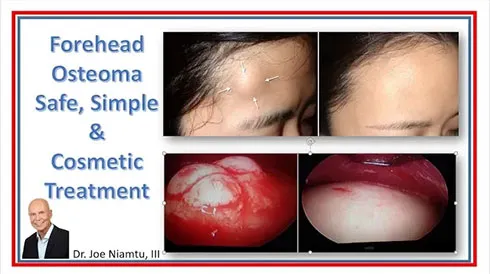

The treatment can frequently be performed with endoscopic technique through a button hole incision. It can be performed with local anesthesia, but due to the instrumentation required to remove the lump and smooth the bone, IV sedation is preferable.

The above image shows the removed osteoma which is about the size of a small peach seed.